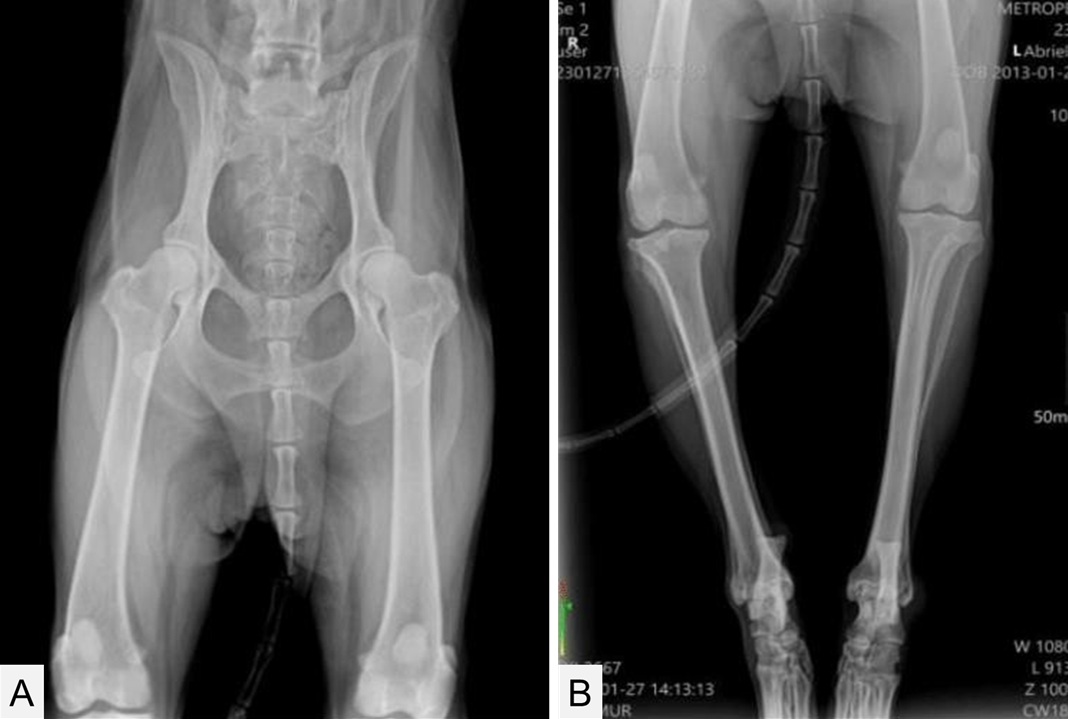

Cover: Andadari, A.Y.D, & Napitu, N. (2025). Pain management approach in a cat with feline arterial thromboembolism assessed using the Feline Grimace Scale. ARSHI Veterinary Letters. 9(3):73-74.